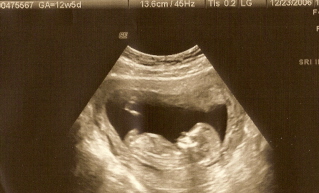

Not 11 wk...here is my 12 wk. 5 day

Image Attachment(s):

WHOAAAAAAAA what a difference from a 10 week

Wow this picture is so clear! The baby is so clear and dark! My pictures don't look this clear! I think your doctor has a better sono machine than mine!

Great pic btw!